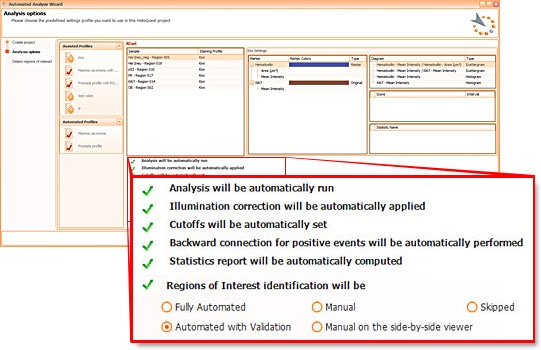

HistoQuest automation

HistoQuests fully automated template based analysis is optimised for clinical routine and research applications and allows complete walk away operation.

HistoQuests fully automated template based analysis is optimised for clinical routine and research applications and allows complete walk away operation.

The user just has to load samples into the software and to decide whether he wants samples automatically detected (in which case analysis will start immediately), whether he wants to be able to interfere with automatic region detection (with validation) or whether he wants to manually define regions to be analysed.